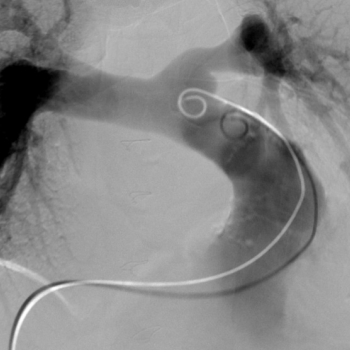

Centrum komplexní péče o vrozené srdeční vady v dospělosti vzniklo  v roce 2015  díky spolupráci  Centra kardiovaskulární a transplantační chirurgie s Interní kardiologickou klinikou Fakultní nemocnice  Brno a nabízí zcela komplexní péči o dospělé nemocné s vrozenou srdeční vadou. Portfolia jednotlivých pracovišť se navzájem doplňují.  Centrum poskytuje ambulantní sledování pacientů se všemi typy vrozených srdečních vad, neinvazivní a invazivní diagnostiku včetně transesofageální echokardiografie s využitím 3D zobrazení.  Centrum kardiovaskulární a transplantační chirurgie Brno provádí operace, reoperace a  intervenční výkony u vrozených srdečních vad a současně se věnuje chirurgické léčbě pokročilého srdečního selhání vč. implantace mechanických srdečních podpor a transplantace srdce ( Tým lékařů , seznam prováděných operačních a intervenčních výkonů).  V rámci Interní kardiologické kliniky FN Brno poskytuje invazivní  řešení arytmií ( radiofrekvenční ablace, kardiostimulace vč. resynchronizační léčby), některé intervence (uzávěry defektů septa síní) , organizaci nekardiálních operací a péči o gravidní včetně porodu probíhají v rámci Interní kardiologické kliniky FN Brno.   Návaznost na kardiologii dětského věku je zajištěna spoluprací s Fakultní dětskou nemocnicí v Brně.  Ambulantní péče probíhá na obou klinikách paralelně.